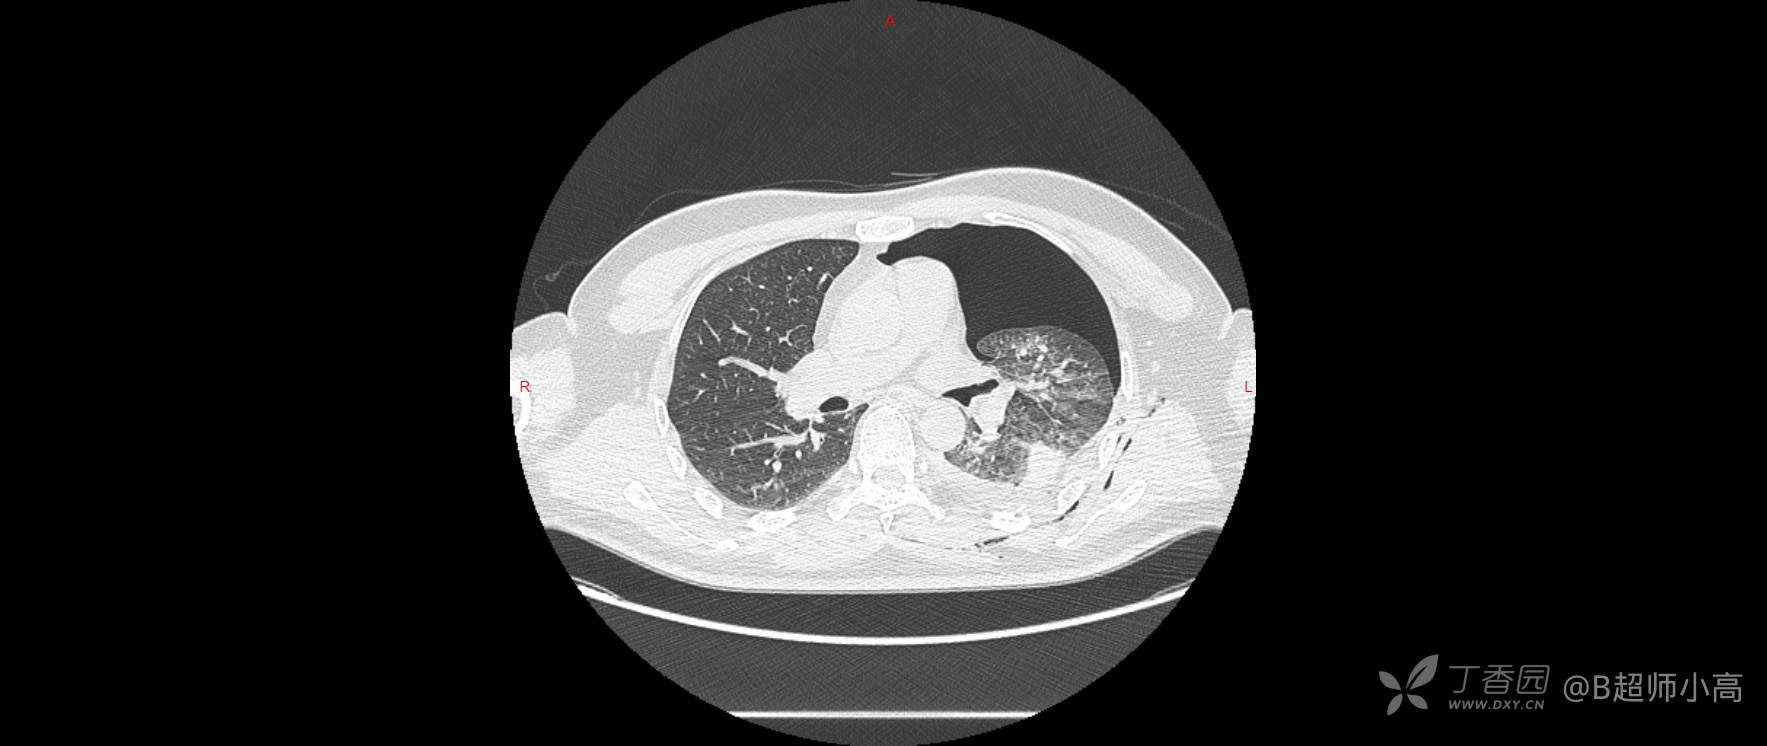

CT结果